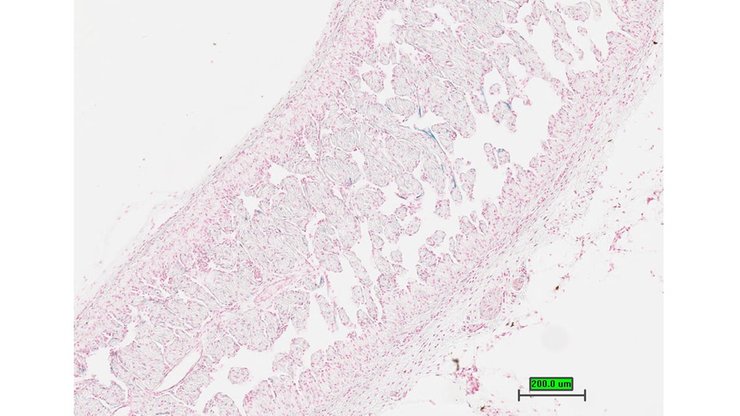

TS28: lung Present UC Davis_1864628